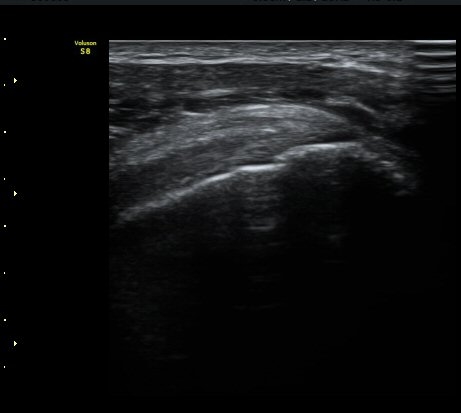

±Ø»ó°Ç Á¾´Ü¸é°Ë»ç¿¡¼­ ±Ø»ó°Ç ÆÄ¿­Àº º¸ÀÌÁö ¾ÊÀ¸³ª »ó¿Ï°ñ ´ë°áÀý°ú °ñµÎ ÀÌÇàºÎÀ§¿¡¼­

ÇÇÁú°ñ ¿¬°á ¼Ò½Ç°ú ¹Ì¼¼ÇÑ °ñÆíÀÌ °üÂûµÊ(»çÁø 3, 4, 5).

±Ø»ó°Ç Ⱦ´Ü¸é°Ë»ç¿¡¼­ ±Ø»ó°Ç ±ÙÀ§ºÎ¿¡¼­´Â ƯÀÌ ¼Ò°ßÀ» º¸ÀÌÁö ¾ÊÀ¸³ª ±Ø»ó°Ç ¿øÀ§ºÎ¿¡¼­

ÇÇÁú°ñ ¿¬°á ¼Ò½Ç°ú ¹Ì¼¼ÇÑ °ñÆíÀÌ °üÂûµÊ(»çÁø 6, 7).